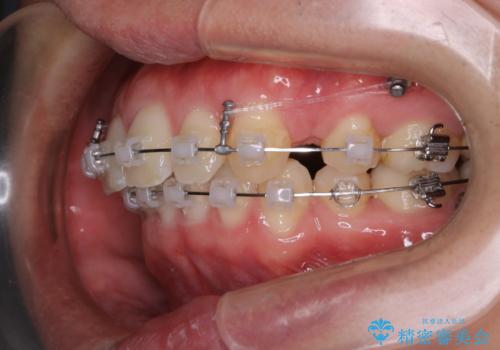

- 矯正装置

- ワイヤー矯正 審美装置

もともとの歯の根っこの位置の関係で、治療途中において上下の真ん中の位置がずれてしまいました。機能的には問題ありませんが患者様と相談し、期間を延ばした上で真ん中を合わせる治療を追加で行いました。

今回のように歯を大きく動かす場合、インビザライン治療ではどうしても歯が傾いてしまう場合があります。

ワイヤー治療では歯の傾きを抑えながら大きい距離の移動が可能で、かみ合わせが深くなるリスクも少ないです。